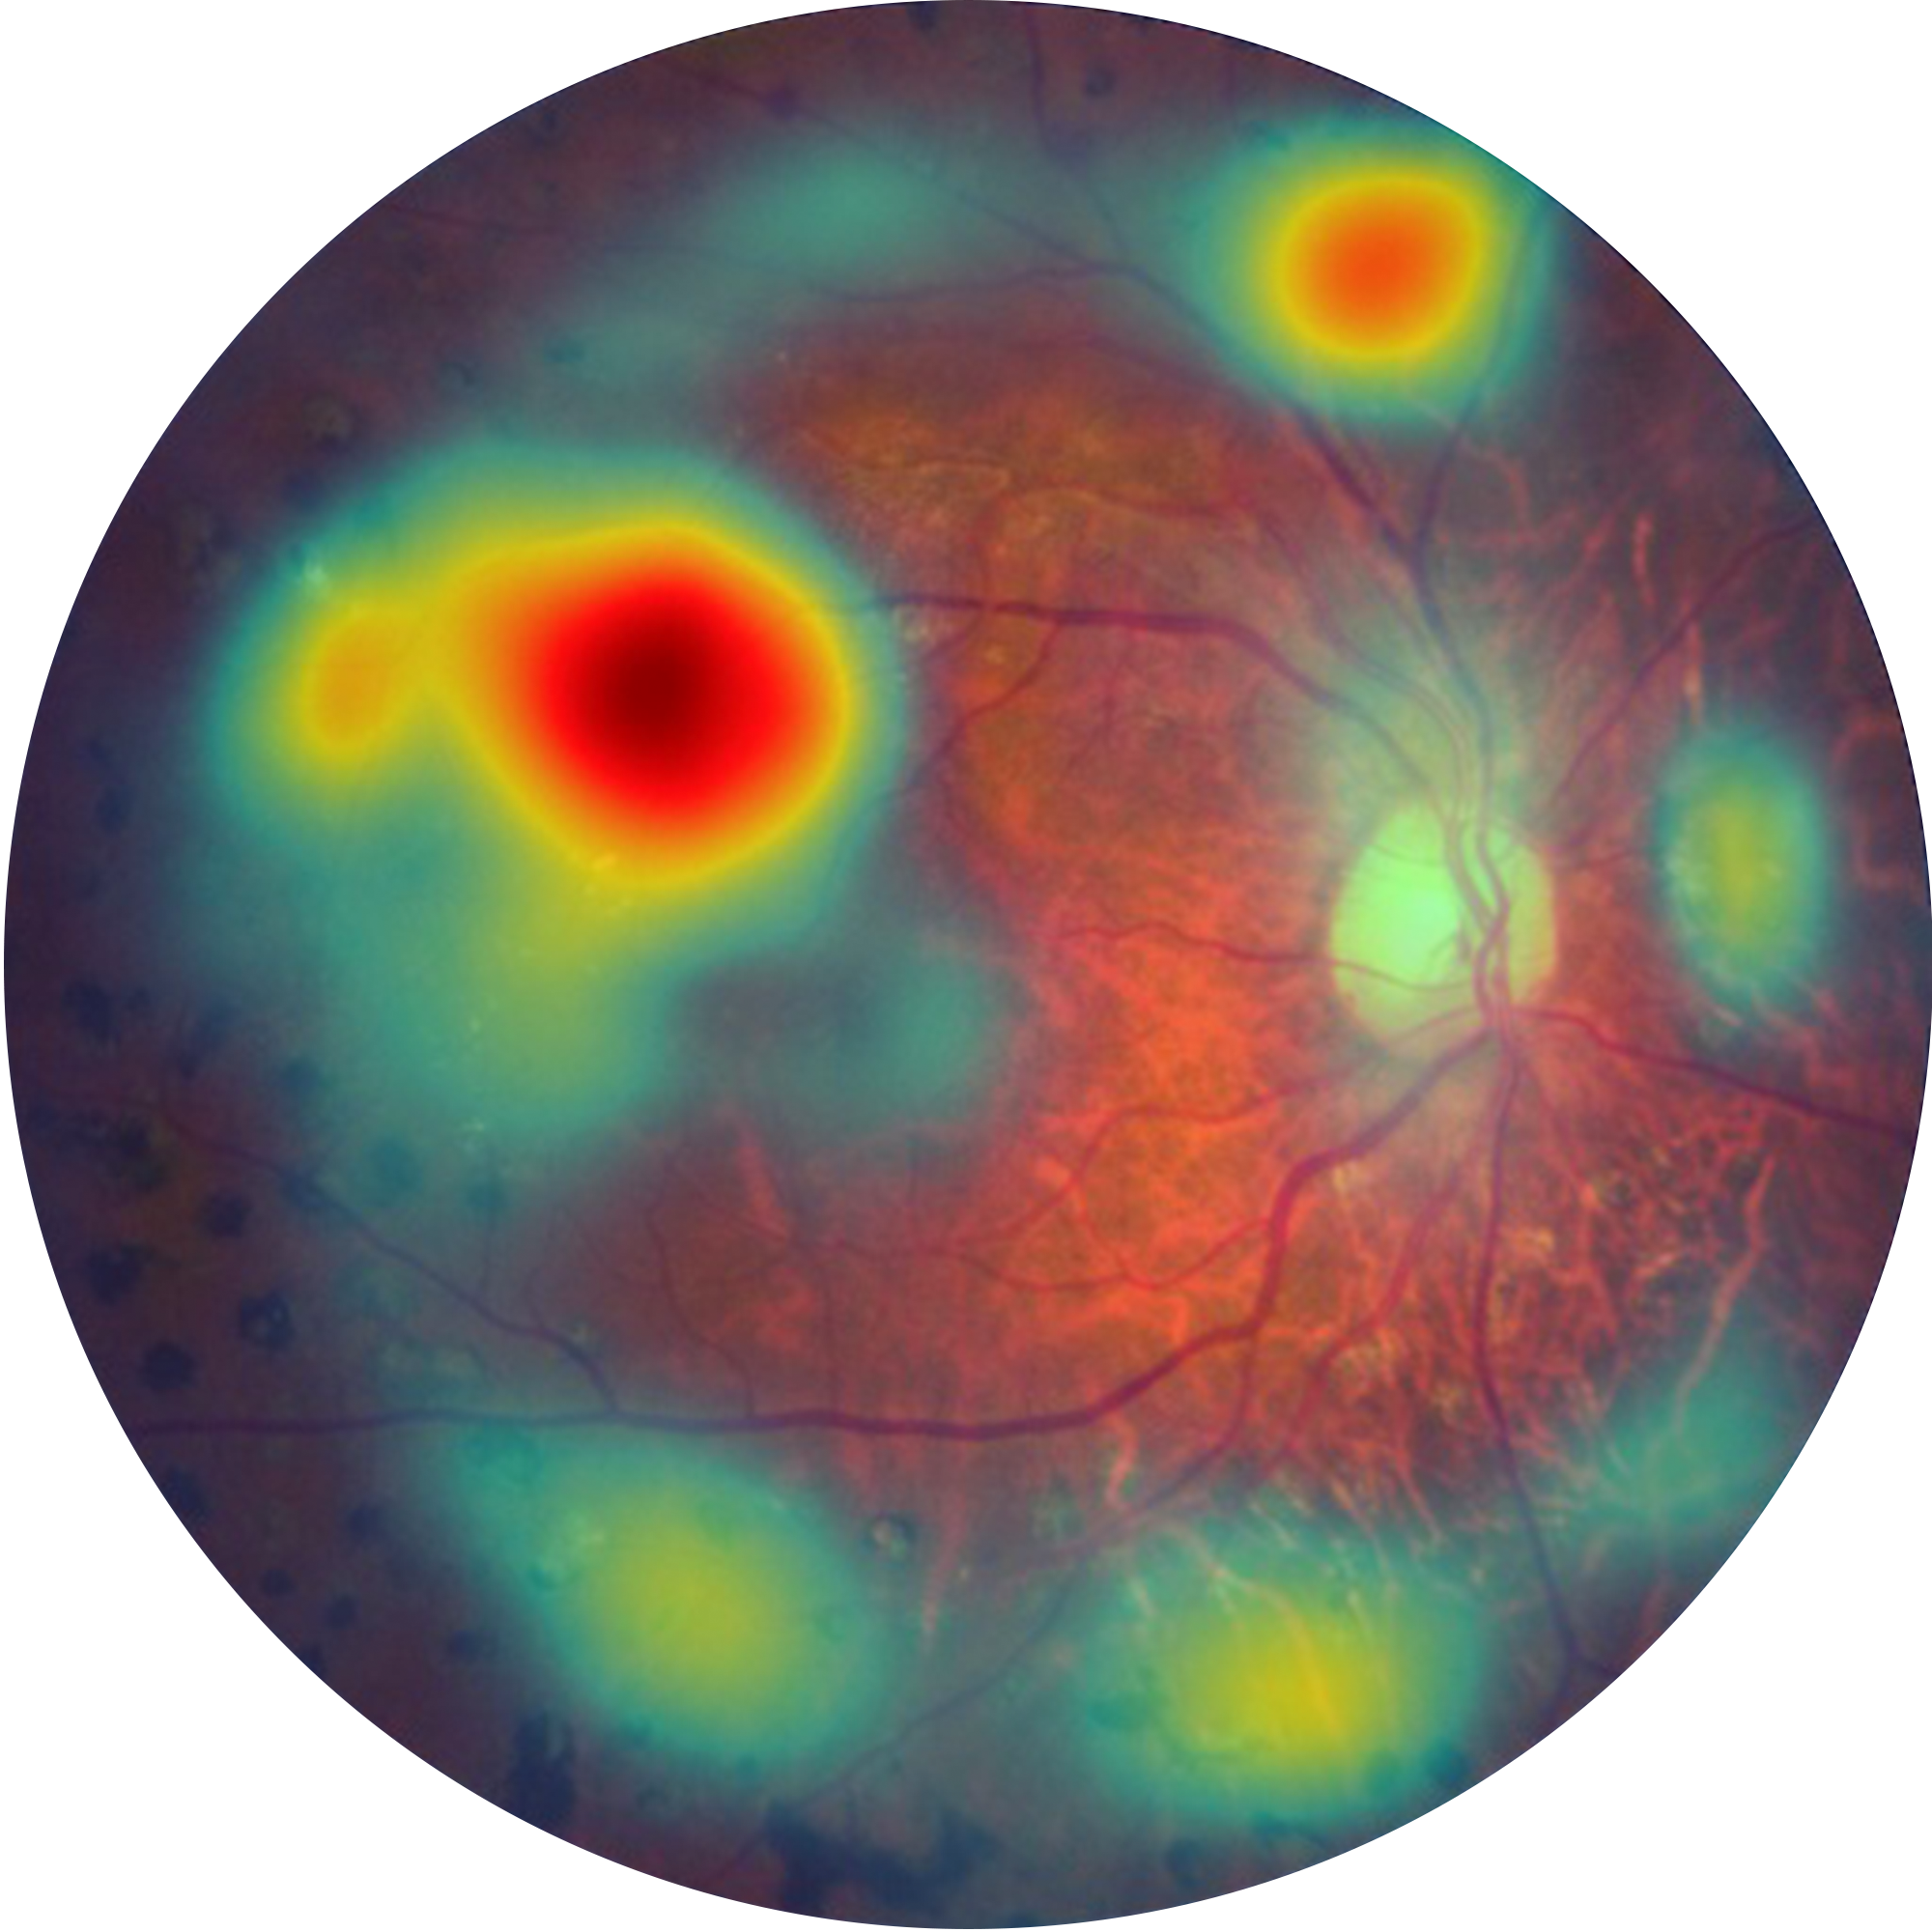

Automatically detects signs of referable DR in under 7 seconds—fully offline, enabling rapid screening at the point of care.Structured reports with visual heatmaps highlight regions of interest, aiding patient counselling and supporting clinical referral decisions